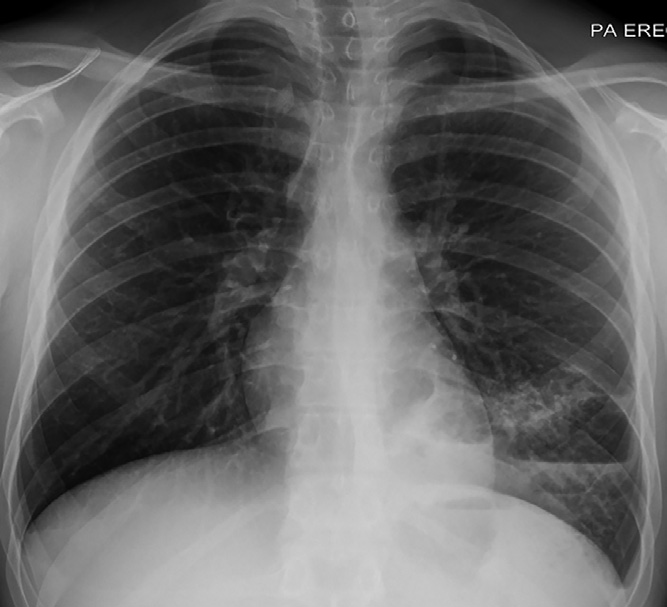

實(shí)驗(yàn)室檢查顯示白細(xì)胞計(jì)數(shù)13.6×109/L↑(中性粒細(xì)胞79%;淋巴細(xì)胞12%),C反應(yīng)蛋白96 mg/L↑。胸部X線檢查顯示左肺下葉實(shí)變伴氣液平面,考慮與空洞性肺炎相關(guān)(圖1)。增強(qiáng)CT顯示左肺下葉病變,有空氣支氣管征和含氣液平面的空洞及囊狀氣腔。(圖2A–2 C)。人類免疫缺陷病毒抗體檢測、抗中性粒細(xì)胞胞漿抗體、尿肺炎球菌和軍團(tuán)菌抗原檢測均為陰性,且多組血培養(yǎng)結(jié)果顯示無菌?;颊呦惹拔催M(jìn)行IgG及亞類缺陷檢測。

圖1 胸部X線顯示左肺下葉實(shí)變伴氣液平面,未發(fā)現(xiàn)明確腫塊。該結(jié)果與空洞性肺炎相關(guān)。